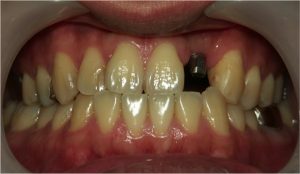

インプラント埋入後、約8週後のインプラントの写真です(写真2)。

↑実際の写真2 インプラント治療後、8週間目の状態です。